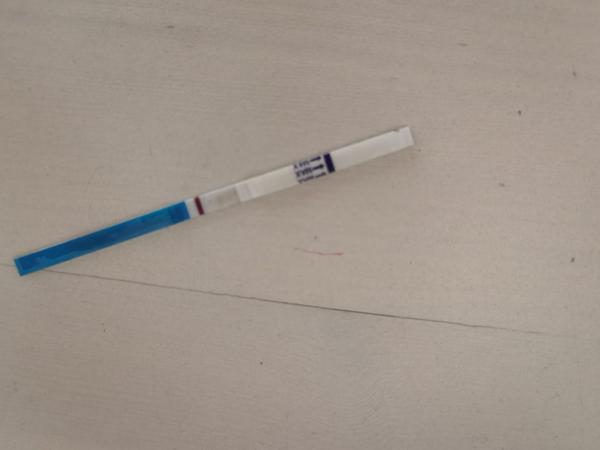

ahojte babule, mam taku otazku...mate skusenost ze pocas 3 dni vam nesilnela druha ciarka na teste ale bola rovnaka???ako duch????

Ahojte baby potrebujem radu dnes som 9-10dpo, od včera mi je zle na žalúdku, vracala som, aj dnes mi je tak isto, tak je mi cudne... A test som si spravila až teraz poobede a nič tam špeciálne nevidím vy áno? Viem ze je to skoro, ale nedalo mi tak som si test spravila a zatiaľ tam nič nie je iba taky ako duch alebo len kanálik 🤔 neviem ťažko povedať..

@tinadeville no tebe to vidno pekne, ja som to mala takto isto voľným okom to lepšie bolo vidno